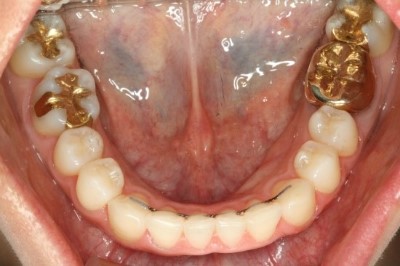

자 그럼 교정 후에 치열이 어떻게 바뀌었는지 한 번 볼까요?

유지장치가 부착되어 있는 것이 보이시죠?